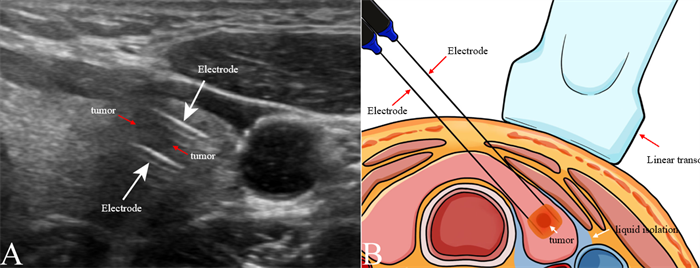

纳秒刀消融PTMC示意图。

此次研究中,纳秒刀消融全程依赖超声引导,这一技术保障了治疗的精准性和安全性。超声作为实时、无创的影像手段,能够清晰显示肿瘤的位置、大小、形态,以及与喉返神经、气管等周围结构的关系,帮助医生精准定位电极位置,确保消融范围完全覆盖肿瘤,同时避开重要组织。术后即刻通过超声造影(CEUS),可直观判断消融效果,若消融范围不足可及时补充治疗,进一步提升疗效。